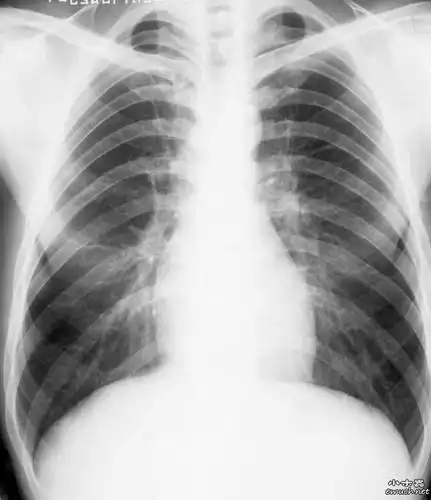

求助正常肺部x光片图片供教学用

肺部x射线图像

肺部x光

肺部正常和x线异常表现ppt